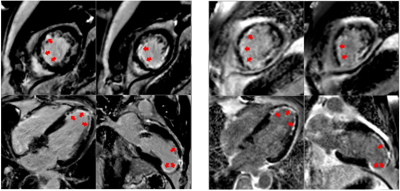

Scans show cardiovascular impact lingers after the acute phase of viral infection and into recovery.